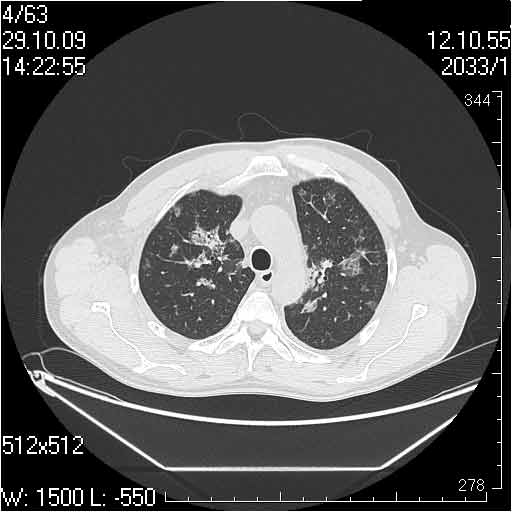

Случай №2

Мужчина 54 лет

Случай 2: картина патологических изменения довольно типична: GGOs & thickened interlobular septas = "crazy paving" sign. Наличие плотностей по типу матового стекла в сочетании с утолщением междолевых перегородок, даёт признак булыжной мостовой; на первом месте будет стоят диагноз альвеолярных протеиноз.